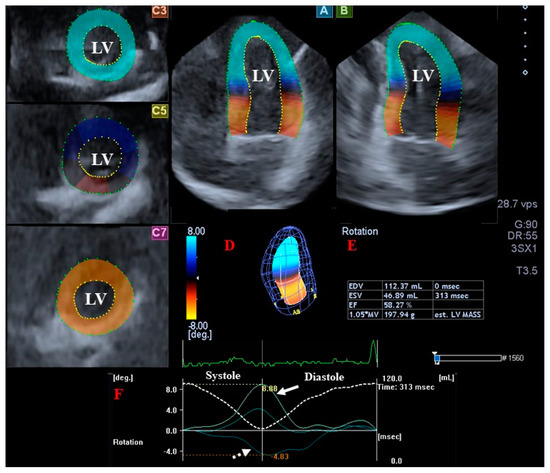

2.4. 3DSTE-Derived Determination of LV Twist

- Clockwise basal LV rotation (in degrees);

- Counterclockwise apical LV rotation (in degrees);

- LV twist (net difference between LV apical and basal rotations in degrees);

- Time-to-peak LV twist (in milliseconds).